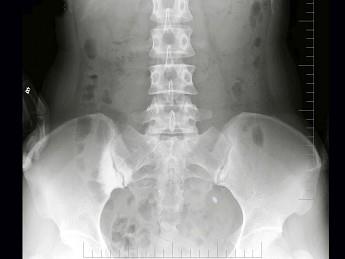

问题 女,26岁,骶髂部疼痛2年余,间歇发作,结合图像,最可能诊断是?(?)

选项 A.致密性髂骨炎 B.化脓性髂骨炎 C.结核性髂骨炎 D.强直性脊柱炎 E.骶髂关节退行性变

答案 A